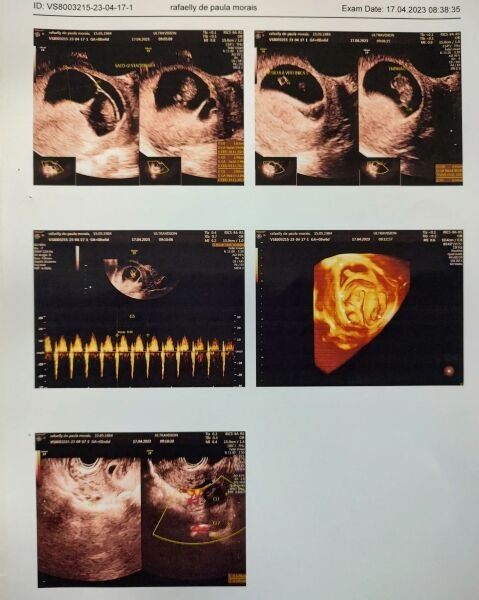

Pais de primeira viagem, o casal compartilhou os primeiros momentos dos filhos nas redes sociais. "Recebemos uma notícia que mudou nossas vidas, descobrimos que estava gestante, mas a maior surpresa estava por vim, tinha 05 bebês no forninho sendo 4 sacos gestacionais, 1 deles contendo 2 bebês. Esse é o início de novas vidas em nossas famílias", escreveram.

Com 9 semanas, equivalente a três meses, os quíntuplos estão se desenvolvendo com saúde, porém o caso de Rafaelly é delicado, uma vez que mulheres que engravidam após os 35 anos enfrentam grandes riscos de complicações, tanto relativas ao parto, quanto ao bebê que está por vir. Imagine isso multiplicado por cinco.